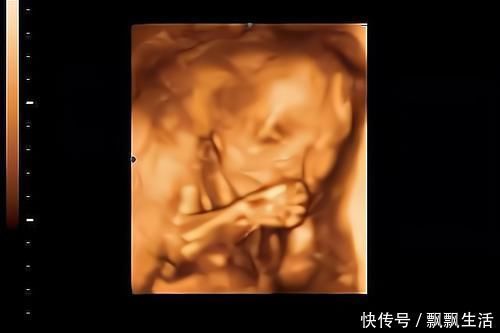

3.对孕妈的抚摸有反应

孕妈们可能会有这样的经历,当抚摸肚子,给宝宝做胎教、和宝宝说话时,胎宝宝可能很欢脱、很活跃。

不同性格的胎儿,对胎教时的表现也不一样。

性格偏安静、比较懒的宝宝,就算有“胎教刺激”时,也不一定会有反应。

而性格偏活泼好动的胎儿,当有“胎教刺激”时,会和妈妈“互动”的很欢,很愿意玩。